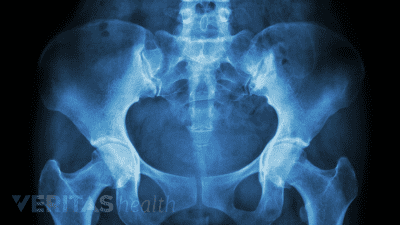

Discover the best radiographic tests for diagnosing SI joint dysfunction and ruling out serious medical conditions.